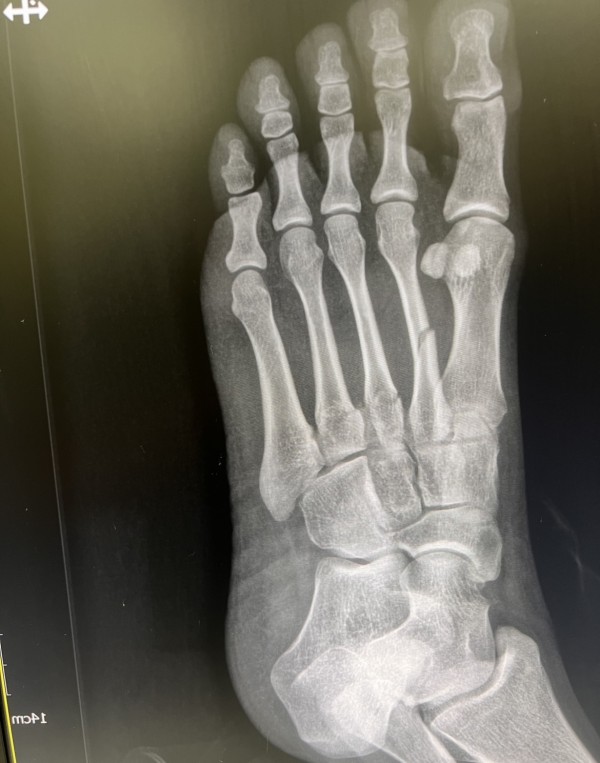

김지범원장 중족골골절

올렸는데, 안떠서 같은사진두장,, 사진재첨부해드립니다! 감사합니다